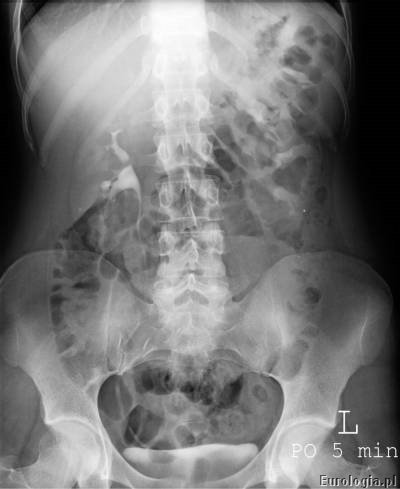

Kolejną fazą w badaniu jest faza wydzielnicza, w czasie której uwidocznione zostają układ kielichowo- miedniczkowy i moczowody. Urolog na podstawie zdjęć urograficznych ocenia nerki i moczowody pod kątem obecności w nich złogów, wad anatomicznych – np. zwężenie połączenia miedniczkowo – moczowodowego lub nowotworów. Nowotwory urothelialne występujące w układzie kielichowo – miedniczkowym lub moczowodzie widoczne są jako ubytki wypełnienia. W przeszłości urografia była podstawową metodą rozpoznawania guzów nerki.

Urografia wykonywana jest w pracowni rentgenowskiej i trwa około 30 minut. W czasie badania pacjent układany jest w pozycji leżącej na plecach na stole rentgenowskim. Pierwsze zdjęcie wykonane przed podaniem kontrastu nazywane jest zdjęciem przeglądowym nerek i pęcherza, na którym możliwe jest uwidocznienie cieni mogących być uwapnionymi złogami w układzie moczowym. Kolejnym etapem badania jest dożylne podanie kontrastu przez wenflon wkłuty na przedramieniu pacjenta. Po podaniu kontrastu wykonywana jest seria zdjęć rentgenowskich w odpowiednich odstępach czasu. Czasami konieczne jest wykonanie tak zwanych późnych zdjęć urograficznych w sytuacji gdy w standardowym czasie nie uzyskano zakontrastowania układu kielichowo – miedniczkowego lub moczowodu.

Przykładowe badanie urograficzne :